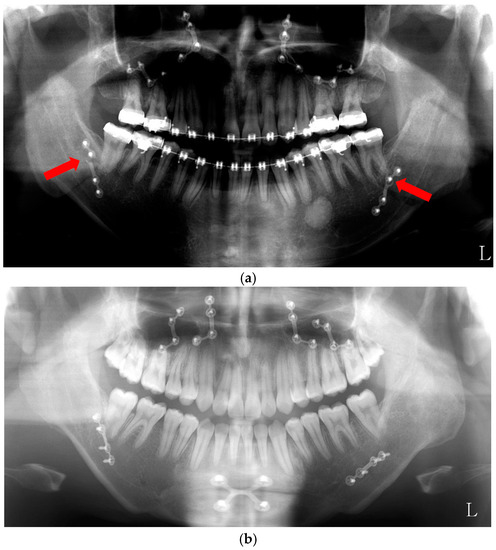

- Mücke, T.; Löffel, A.; Kanatas, A.; Karnezi, S.; Rana, M.; Fichter, A.; Haarmann, S.; Wolff, K.D.; Loeffelbein, D.J. Botulinum toxin as a therapeutic agent to prevent relapse in deep bite patients. J. Craniomaxillofac. Surg. 2016, 44, 584–589. [Google Scholar] [CrossRef] [PubMed]

- Seok, H.; Park, Y.T.; Kim, S.G.; Park, Y.W. Correction of post-traumatic anterior open bite by injection of botulinum toxin type A into the anterior belly of the digastric muscle: Case report. J. Korean Assoc. Oral Maxillofac. Surg. 2013, 39, 188–192. [Google Scholar] [CrossRef] [PubMed]

- Shin, S.H.; Kim, S.G.; Park, Y.W.; Kim, M.K.; Kweon, K.J. The effect of Botulinum toxin-A injection on patients with orthognathic surgery. In Proceedings of the 56th Congress of the Korean Association of Maxillofacial Plastic and Reconstructive Surgeons, Seoul, Korea, 3–4 November 2017; p. 31. [Google Scholar]